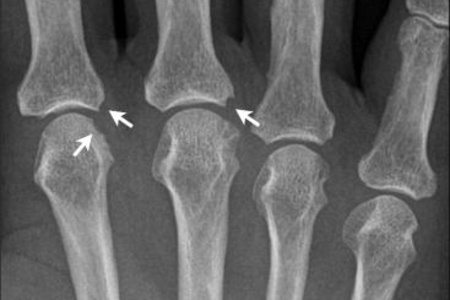

Рентгенологические исследования. Снимки костей помогают выявить характерные изменения, однако их можно заметить только при потере более трети костной массы. Лечение остеопороза на этой стадии представляет значительные трудности.

Компьютерная томография. Этот метод обеспечивает раннюю диагностику и эффективное лечение. Однако его недостаток — невозможность обследовать весь скелет одновременно, что делает процесс томографического исследования трудоемким.